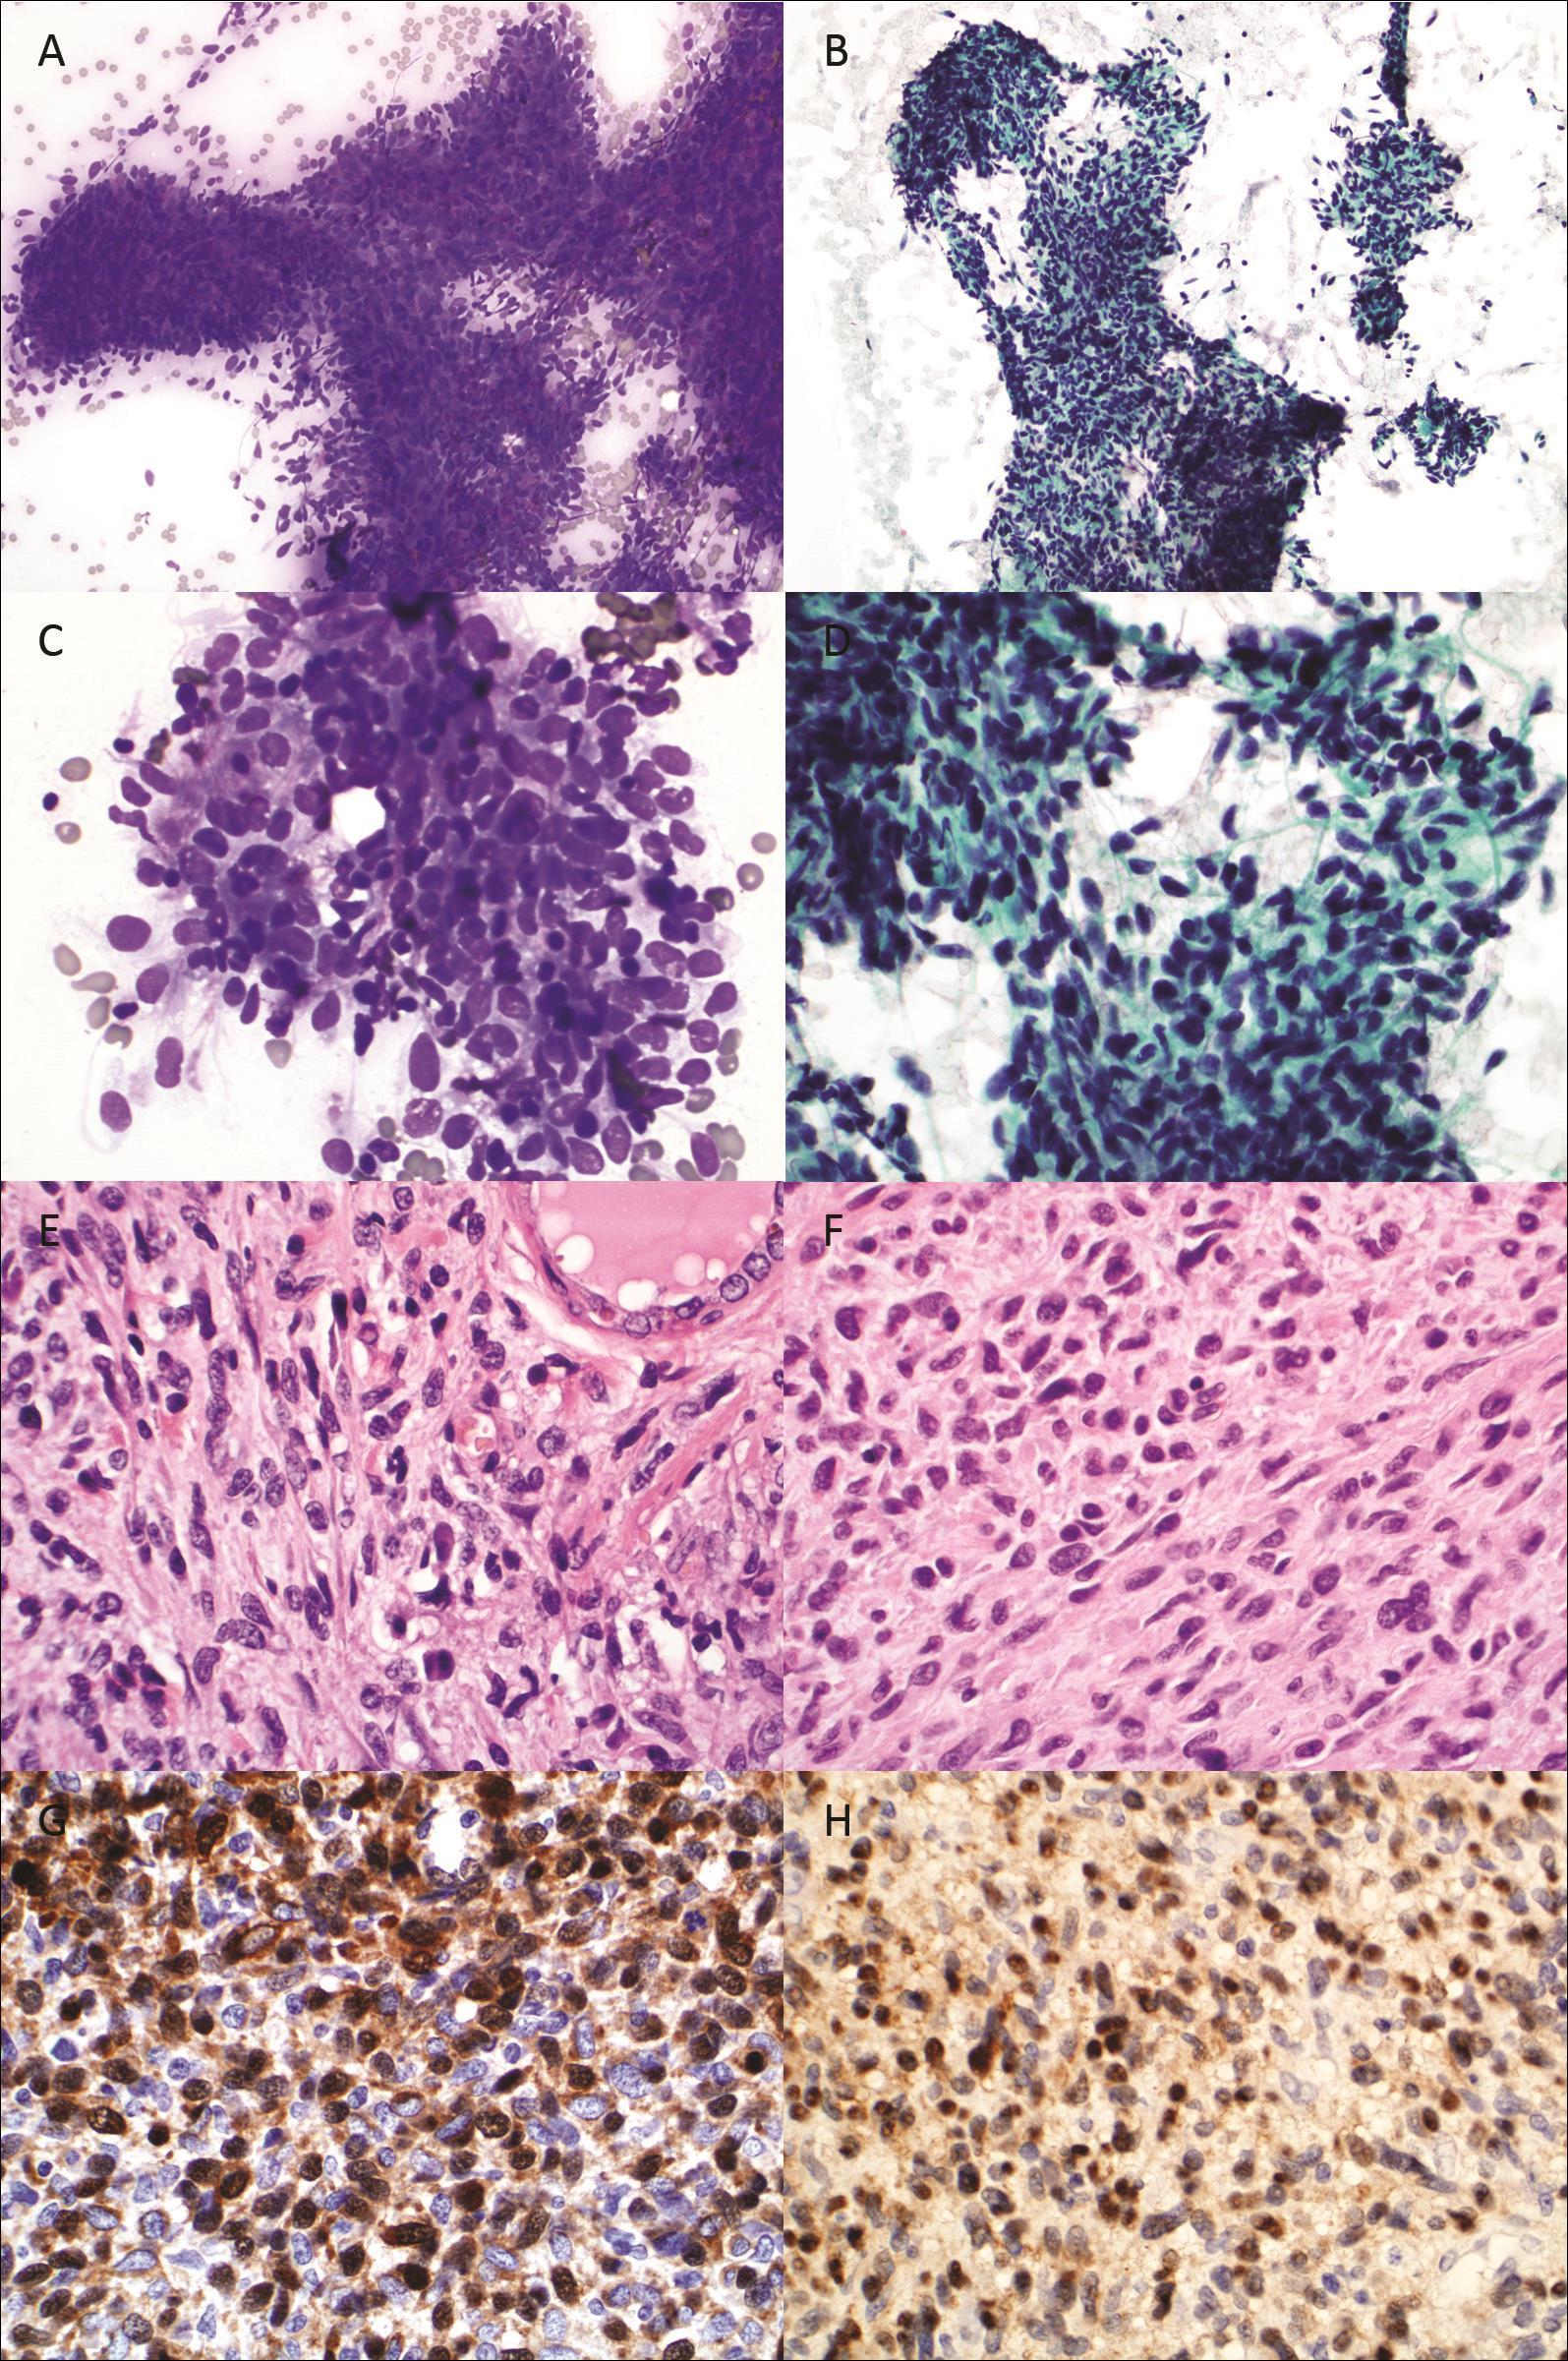

An ultrasound guided fine needle aspiration (FNA) was performed using 25 gauge needles on the right thyroid nodule.The air-dried FNA slides were stained with Diff-Quik stain and ethanol fixed slides were stained with Papanicolaou stain. Microscopic examination showed numerous loosely cohesive pleomorphic small spindle cells, some of which were arranged in short fascicles or haphazard pattern (Figure 1A to 1D).

Figure 1A and 1B.FNA cytology, Diff-Quik and Papanicolaou stain, respectively, x200. Fig. 1C and 1D: FNA cytology, Diff-Quik and Papanicolaou stain, respectively, x600. Fig. 1E and 1F: Histology from thyroid and small intestine, hematoxylin and eosin, x600. Fig. 1G and 1H: Immunostain for S100 on thyroid and small intestine, x600.

The nuclei were oval or spindle in shape, with hyperchromatic granular chromatin and inconspicuous nucleoli, and smooth nuclear membrane contours. The cytoplasm was scant to moderate in amount, and delicate. Some cells had long thin cytoplasmic projections. Normal thyroid follicular cells and colloid were present in the background. The cytomorphology of the current specimen was similar to that seen in the tumor of previous small intestine resection, while was different

from that seen in the previously resected melanoma. Based on the cytomorphology, a diagnosis of “consistent with metastatic MPNST from small intestine” was rendered.

Subsequently he underwent a total thyroidectomy. The thyroidectomy specimen demonstrated a white-pink lobulated mass measuring, 1.7 x 1.2 x 1.2 cm and several smaller nodules. The tissue containing tumor was formalin fixed, paraffin embedded, sectioned, and stained with hematoxylin and eosin (H&E) stain. The tumor was composed of sheets of pleomorphic spindle cells with cytomorphologic features similar to those seen in the FNA cytology. The tumor cells were arranged in fascicle or haphazard patterns. A high mitotic rate of 10 per 10 high power fields was noted (Figure 1E). The histology of the thyroid nodule was similar to that seen in the prior sarcoma of resected from the small intestine Figure 1F). Both the tumors were focally positive for S100 (Figure 1G and 1H). The thyroid tumor was negative HMB-45 and melan A. The histologic features and immunoprofile confirmed the cytologic diagnosis.